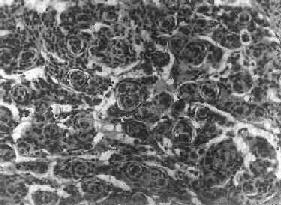

图16-25 室管膜瘤

瘤细胞为圆形或卵圆形,核染色质丰富,胞浆少,可见有细长的胞浆突起与血管相连,呈放射关,形成假菊形团